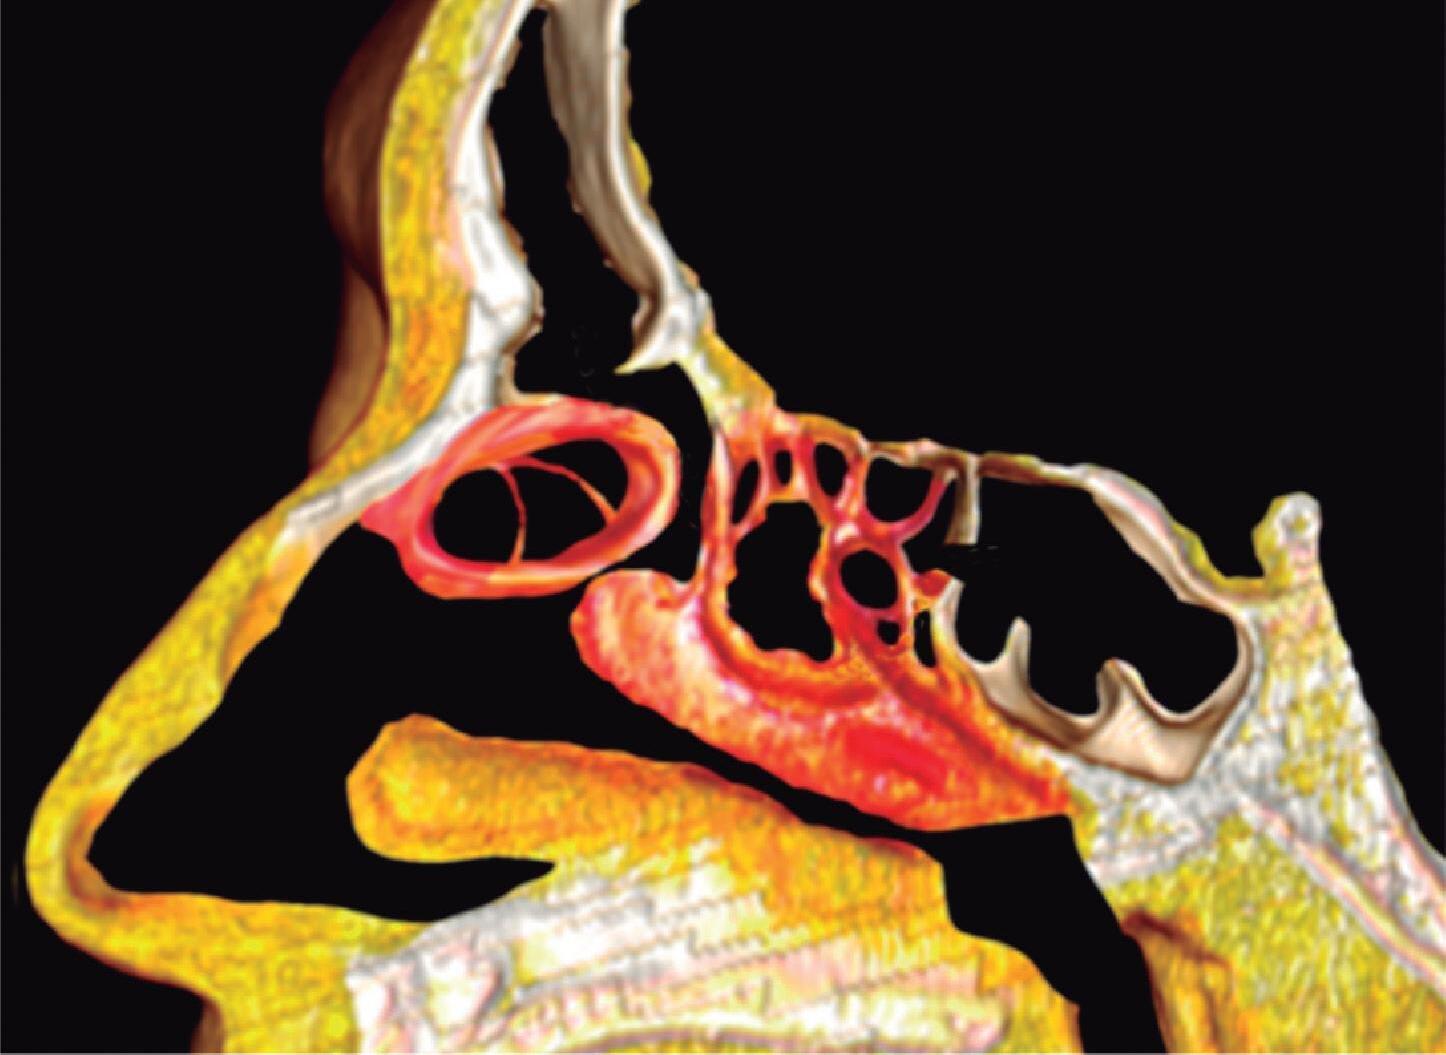

1-4. TC e reconstrução 3D com destaque para estrutura etmoidal (em vermelho), funcionando como câmaras de baixa pressão para drenagem do seio maxilar.

1-7. TC com reconstrução 3D mostrando em vermelho apenas o seio etmoidal e não o osso etmoidal, e sua relação com a fossa nasal, o seio maxilar, órbita e fossa anterior.

Este complexo anatômico chamado seio etmoidal, controla a pressão e o fluxo aéreo que penetra nos verdadeiros seios paranasais e pode ser interpretado como um sistema de câmaras aerodinâmicas de baixa pressão cuja topografia particular faz dele o centro anatomofuncional do aparelho rinossinusal.

Na estrutura do seio etmoidal as câmaras aerodinâmicas denominadas meatos, oferecem um espaço fisiológico definido para os seios esfenoidal, maxilar e frontal e são dispostas arquitetonicamente para impedir que o fluxo inspiratório (rápido, frio e seco) penetre nestas cavidades, e permitir a entrada do fluxo expiratório (lento, aquecido e úmido). Existem pelo menos duas e as vezes três câmaras etmoidais na parede lateral do nariz que são os meatos, médio, superior e supremo.